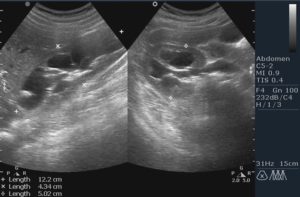

- УЗИ позволяет оценить форму и размер лоханок, чашечки, локализацию почечных структур, расположение вен. Исследование является безопасным для грудничков и выявляет патологию почек в утробе.

- 1 этап — пиелоэктазия. Характеризуется умеренным изменением размеров почки, что не оказывает негативное влияние на функционирование органа. Нарушений фильтрации и кровообращения не отмечается. Данный вид патологии диагностируется случайно на плановом ультразвуковом исследовании плода на 16-20 неделях беременности. После рождения врожденная патология у грудничка может быть обнаружена на плановом УЗИ брюшной полости в первый месяц жизни.

Патология обнаруживается случайно на плановом УЗИ во время беременности или в течение первого года жизни. При расширении лоханок почек у ребенка необходимо наблюдаться в детского уролога.

Также, раз в 3 месяца необходимо проходить плановое ультразвуковое исследование для исследования размеров и состояния органа в динамике.

Как же определить, увеличена ли лоханочная капсула у новорожденного? Данное нарушение невооруженным глазом не увидишь. Его диагностируют лишь квалифицированные врачи во время выполнения ультразвукового или другого инструментального исследования.

Такой метод обнаружения патологии не вызывает у детей болезненных ощущений и считается абсолютно безопасным. Проводить подобную процедуру разрешается даже грудничкам. Наличие любых отклонений требует регулярного посещения специалиста для проведения УЗИ и постоянного наблюдения за состоянием здоровья малыша.

Во время обследования доктор видит состояние и размеры мочевыводящих путей на мониторе. Повод для беспокойства есть в том случае, когда УЗИ показало следующие нарушения: